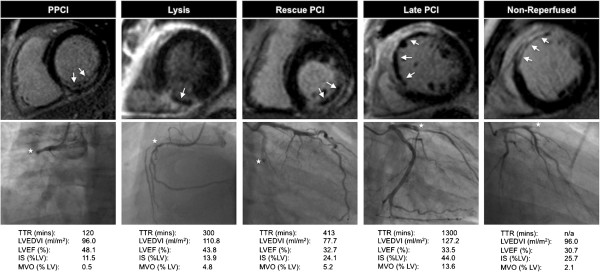

AAR was significantly larger in the late PCI group compared with those undergoing the 3 alternative reperfusion techniques (p < 0.01 compared with each strategy on subgroup analysis). When corrected for TTR, differences in AAR were only of borderline statistical significant (p = 0.054).The prevalence of MVO was similar in the 5 cohorts. There was a trend towards the extent (% of LV mass) of MVO being greatest in the late PCI group, followed by non-reperfused and R-PCI patients. When corrected for TTR, the difference in MVO with the four reperfusion techniques was not statistically significant. Representative CMR and angiography images from patients in the 5 cohorts are shown in Figure 3.

Figure 3.

Representative images of LGE CMR and coronary anatomy at the start of angiography in the cohorts. Top row: CMR late gadolinium images from a patient within each of the 5 study cohorts, demonstrating infarct (enhancement); microvascular obstruction (arrow) evident as hypointense areas within infarct. Middle row: coronary angiography images at the start of angiography in the same patients demonstrating infarct related artery; white star denotes culprit lesion (right coronary artery in PPCI and lysis patient, left circumflex in rescue-PCI patient, left anterior descending artery in late PCI and non-reperfused patient). Bottom row: Time from symptoms to revascularisation (TTR) and CMR data for the same patients.